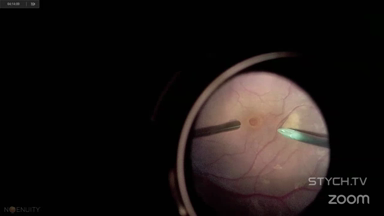

Viewer Discretion Advised: The videos may contain graphic images of surgical procedures that could be disturbing. Viewer discretion is advised. The site is intended for users who are 18 years or older, and no viewers under 18 years of age are allowed unless the use of the site is part of a class within an institution of secondary education and the viewing is supervised by an adult education professional.